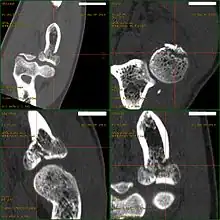

CT scan demonstrating the Mason type III radial head fracture

CT scan showing a radial head fracture